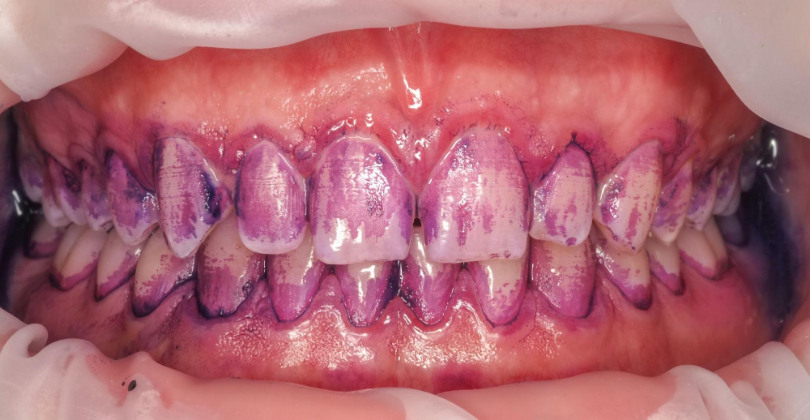

Pacjent zgłaszał się na regularne, co półroczne higienizacje. Wybarwienie płytki nazębnej na pierwszej wizycie ujawniło silne zaleganie płytki nazębnej dojrzałej, kwasowej, gęsto otaczającej zęby (kolor fioletowy). Z każdą kolejną wizytą widać było poprawę higieny i sukces działań higienistki stomatologicznej oraz motywacji własnej Pacjenta. Na trzeciej wizycie po wybarwieniu dostrzegalny jest już tylko delikatny, świeży biofilm. Dzięki technologii GBT posiadamy narzędzia do monitorowania higieny Pacjenta i pozytywnego wzmacniania jego dobrych nawyków.

Pacjent posiada koronę na implancie, która wykorzystywana jest w leczeniu ortodontycznym. W ocenie wizualnej nic nie wskazywało na problem higieniczny. Widoczna była jedynie struktura i delikatne przebarwienie kleju ortodontycznego. Po wybarwieniu płytki nazębnej, dookoła implantu uwidoczniono bardzo gęstą warstwę płytki nazębnej dojrzałej (czyli obecnej na powierzchni minimum 2 dni), w tym kariogennej czyli kwasowej, mogącej powodować próchnicę zębów sąsiadujących.

Bez wybarwiania, które jest częścią GBT, higienistka nie wykonałaby dokładnego usunięcia warstwy bakteryjnej, nie dostrzegając jej. Brak narzędzi obecnych w GBT (piasek EMS Plus, piaskowanie poddziąsłowe) uniemożliwiałby też oczysczenie okolic szczeliny dziąsłowej, a także przy zamkach ortodontycznych i implantach. Pozostawiony biofilm to źródło procesu zapalnego, bólu i krwawienia dziąseł, próchnicy oraz dezintegracji implantów.